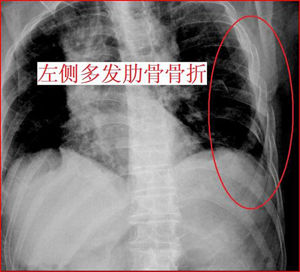

檢查

X線表現多為橫斷形,可有兩處以上骨折線,並可發生移位。側位片顯示更佳。

診斷

根據胸前區撞擊後出現局部疼痛及壓痛可做出初步診斷。如骨折移位,可見局部變形;合併數條肋骨或肋軟骨骨折時,可出現反常呼吸運動,可有呼吸、循環功能障礙。斜位及側位X線片可明確胸骨骨折的診斷。